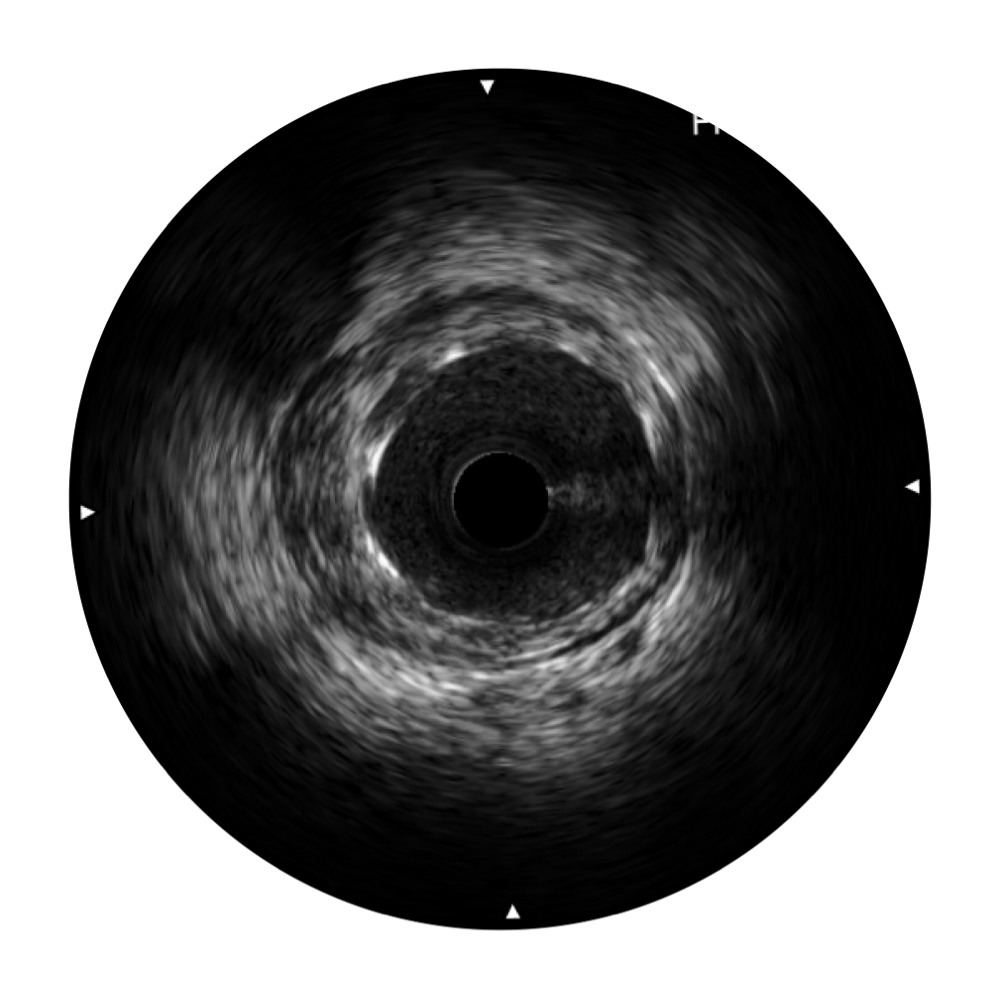

九州酷游宽频IVUS图像

传统IVUS图像

对比传统IVUS导管成像,九州酷游宽频IVUS图像的近场支架梁显影更细腻,远场中膜外血管仍清晰可辨,兼顾远中近,兼顾分辨力与穿透深度